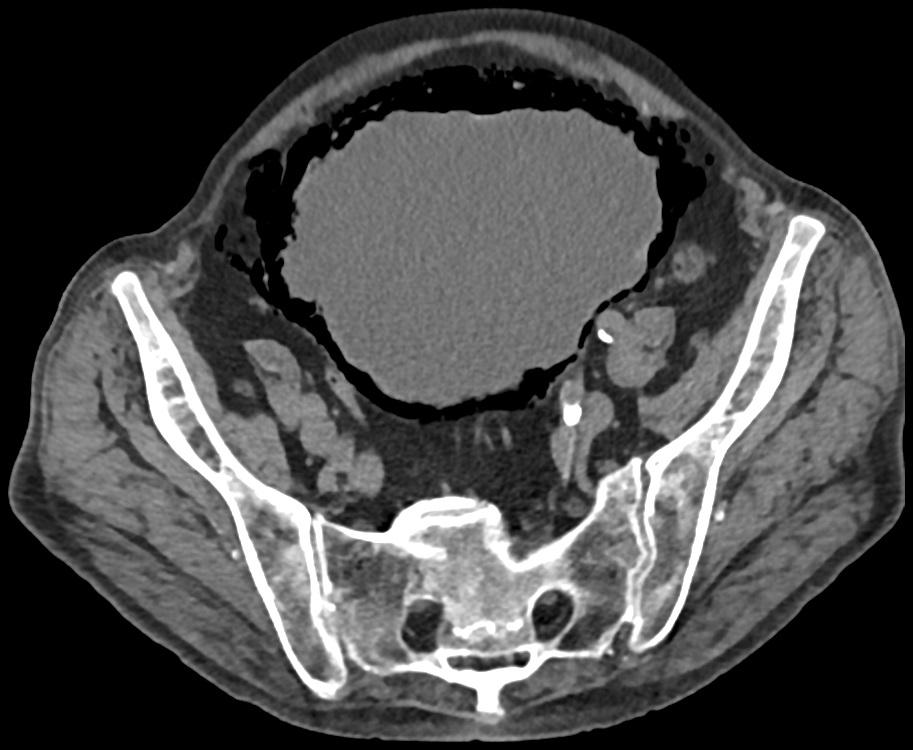

Gepubliceerd: Week 36 - 2018 197 deelnemers Een 74-jarige man komt op de Spoedeisende Hulp na een val van de trap. Bij toeval worden op een CT-scan opvallend uitgebreide, curvilineaire, ovale luchtconfiguraties in de blaaswand gezien. Wat is uw diagnose? Antwoord emfysemateuze cystitis bezoar enterovesicale fistel emfysemateuze pyelonefritis Antwoord controleren